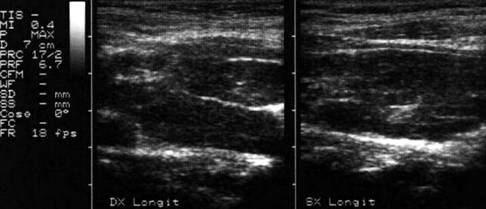

Apexul lobului drept, proiectie longitudinala si trasversala.

Femeie 58 ani. Maladia Graves in tratament cu

metimazol.

Nodul unic in apexul lobului drept, de 11x14x20mm (1,5 cc), hipoecogen, cu

contur difuz

Nu s-a efetuat citoaspiratie.

Aceeasi pacienta. La ecodoppler color - vascularizatie

periferica, avascular intralezional.

Ecopowerdoppler confirma absenta vascularizatiei interne.